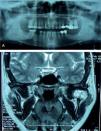

La tomografía axial computarizada (TAC) revela una tumoración de 7 x 2 cm, desde el lóbulo tiroideo izquierdo hasta el cayado aórtico, que produce cierta estenosis traqueal y desplazamiento del esófago (fig. 1).

El paciente permaneció asintomático durante 7 años hasta que acude a la consulta refiriendo disnea y tos de un mes de evolución y en la TAC se objetiva recidiva mediastínica con extensión pulmonar (fig. 3). Se realiza traqueostomía por compresión traqueal del tumor y se inicia tratamiento citotóxico con 4 ciclos de poliquimioterapia. Presentó una supervivencia de un año hasta su fallecimiento por causa tumoral.

En las pruebas de imagen aparece una tumoración de carácter sólido en hemimandíbula izquierda, de 2,5 x 2 x 1,8 cm en la región del cóndilo mandibular, de bordes bien delimitados, que sugiere una lesión agresiva, de probable origen óseo, objetivándose destrucción de rama mandibular izquierda de carácter lítico (fig. 4).